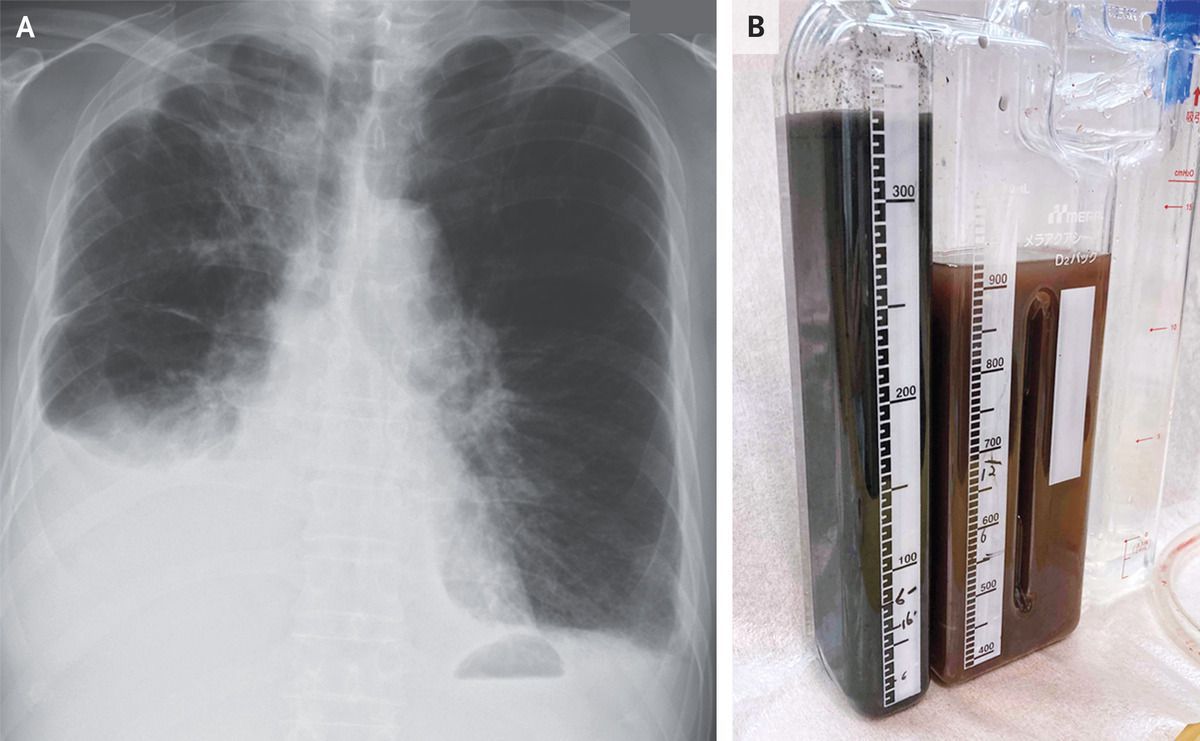

A 77-year-old man with metastatic lung adenocarcinoma presented to the emergency department with a 2-week history of dyspnea. Examination was notable for reduced breath sounds at the right lung base. A chest radiograph showed a pleural effusion on the right side (Panel A). An abdominal ultrasound image showed previously known liver metastases and perihepatic fluid, as well as new intrahepatic dilatation of the biliary ducts. Laboratory studies showed a serum total bilirubin level of 2.5 mg per deciliter (42.8 μmol per liter) (reference range, 0.3 to 1.2 mg per deciliter [5.1 to 20.5 μmol per liter]) and a direct bilirubin level of 2.0 mg per deciliter (34.2 μmol per liter) (reference range, 0.03 to 0.4 mg per deciliter [0.5 to 6.8 μmol per liter]). A chest tube was placed, and the color of the drained pleural fluid was olive brown that gradually changed to black (Panel B). Pleural-fluid studies showed an exudate with a total bilirubin level of 8.2 mg per deciliter (140.2 μmol per liter; reference value, 0) and a direct bilirubin level of 7.5 mg per deciliter (128.2 μmol per liter; reference value, 0). The pleural-fluid triglyceride level was normal, and cultures and cytologic studies were negative. A diagnosis of bilothorax was made. Bilothorax occurs when bile flows into the pleural space. In this case, the mechanism was thought to be diaphragmatic defects caused by hepatic metastases. Two weeks after presentation, the patient died from progressive liver failure.